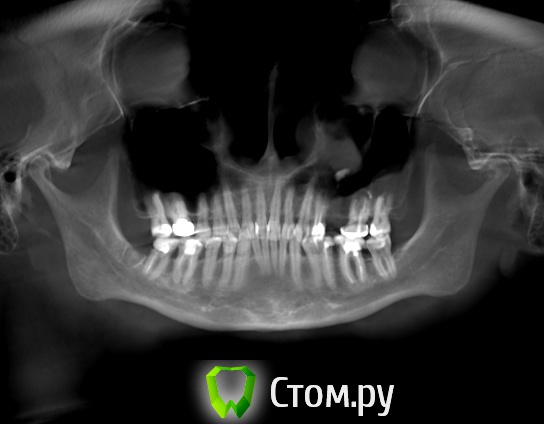

Гуля-Р Опубликовано 1 ноября, 2014 Поделиться Опубликовано 1 ноября, 2014 Добрый день! Ортодонт настаивает на удалении нижних центральных резцов, а не четверок, т.к. для корни нижних резцов подвержены резорбции. Если удалить четверки, то центральные резцы потом расшатаются и надо будет ставить импланты. Удаление резцов приведет к нарушению дикции, да и вид нижних зубов - 2 резца и сразу клыки - не хочется. Как думаете, есть ли шанс, что не потеряю резцы? Пока настроена на удаление четверок, но еще не могу решить. Когда я спросила, тогда расшатаются все 4 нижних резца, ведь корни с резобцией у всех этих резцов, ортодонт ответил, что 2 других резца будут двигать очень медленно и сохранят зубы. Может все 4 резца можно медленно раздвинуть... а потом как-то закрепить ... типа шинирования... Очень нужен совет, извелась вся. Ссылка на комментарий

Force Опубликовано 3 ноября, 2014 Поделиться Опубликовано 3 ноября, 2014 Центральные резцы не удаляются. Ортодонт ваш экстремал. Для комментариев нужны фото. http://forum.stom.ru/topic/4655-patcientam/Четверки на нижней челюсти удалять тоже не нужно. 1 Ссылка на комментарий

Фазлиев Азат Ильдусович Опубликовано 7 ноября, 2014 Поделиться Опубликовано 7 ноября, 2014 Улыбнуться на 6 зубов не получилось, даже помогая пальцами.Внизу вообще без удаления! Только сепарация по необходимости. Ссылка на комментарий

Гуля-Р Опубликовано 9 ноября, 2014 Автор Поделиться Опубликовано 9 ноября, 2014 (изменено) Ну все... нижние центральные резцы отстояла под расписку о том, что в курсе о резорбции и последствиях, удалили нижние четверки, теперь мои скученные зубы долны поместиться в ряд, тем более что удалила внизу единственную восьмерку. Надеюсь не испугаюсь в дальнейшем хирургического вмешательства. В любом случае, зубы должны стать ровнее. Спасибо за ответы. Они помогли мне сделать выбор и не удалить резцы. Изменено 9 ноября, 2014 пользователем Гуля-Р Ссылка на комментарий